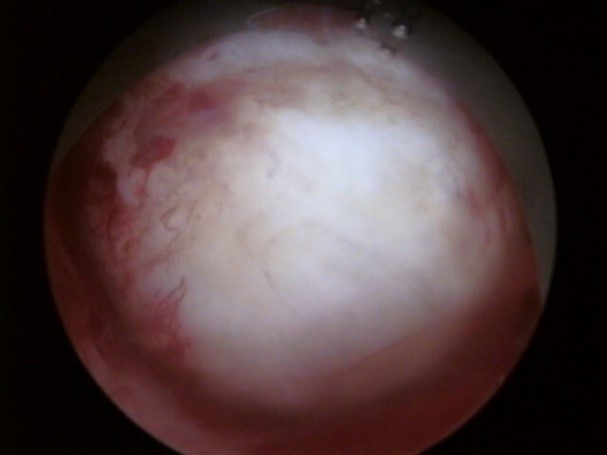

門診軟式子宮鏡檢查

軟式診斷性子宮鏡直徑比硬式子宮鏡細軟,因此通常不需麻醉或禁食即可在門診進行檢查,病患本人可以與醫師一同觀看顯示器討論病情。檢查過程快捷方便,作為子宮腔病變之診斷工具。

軟式子宮鏡適應症